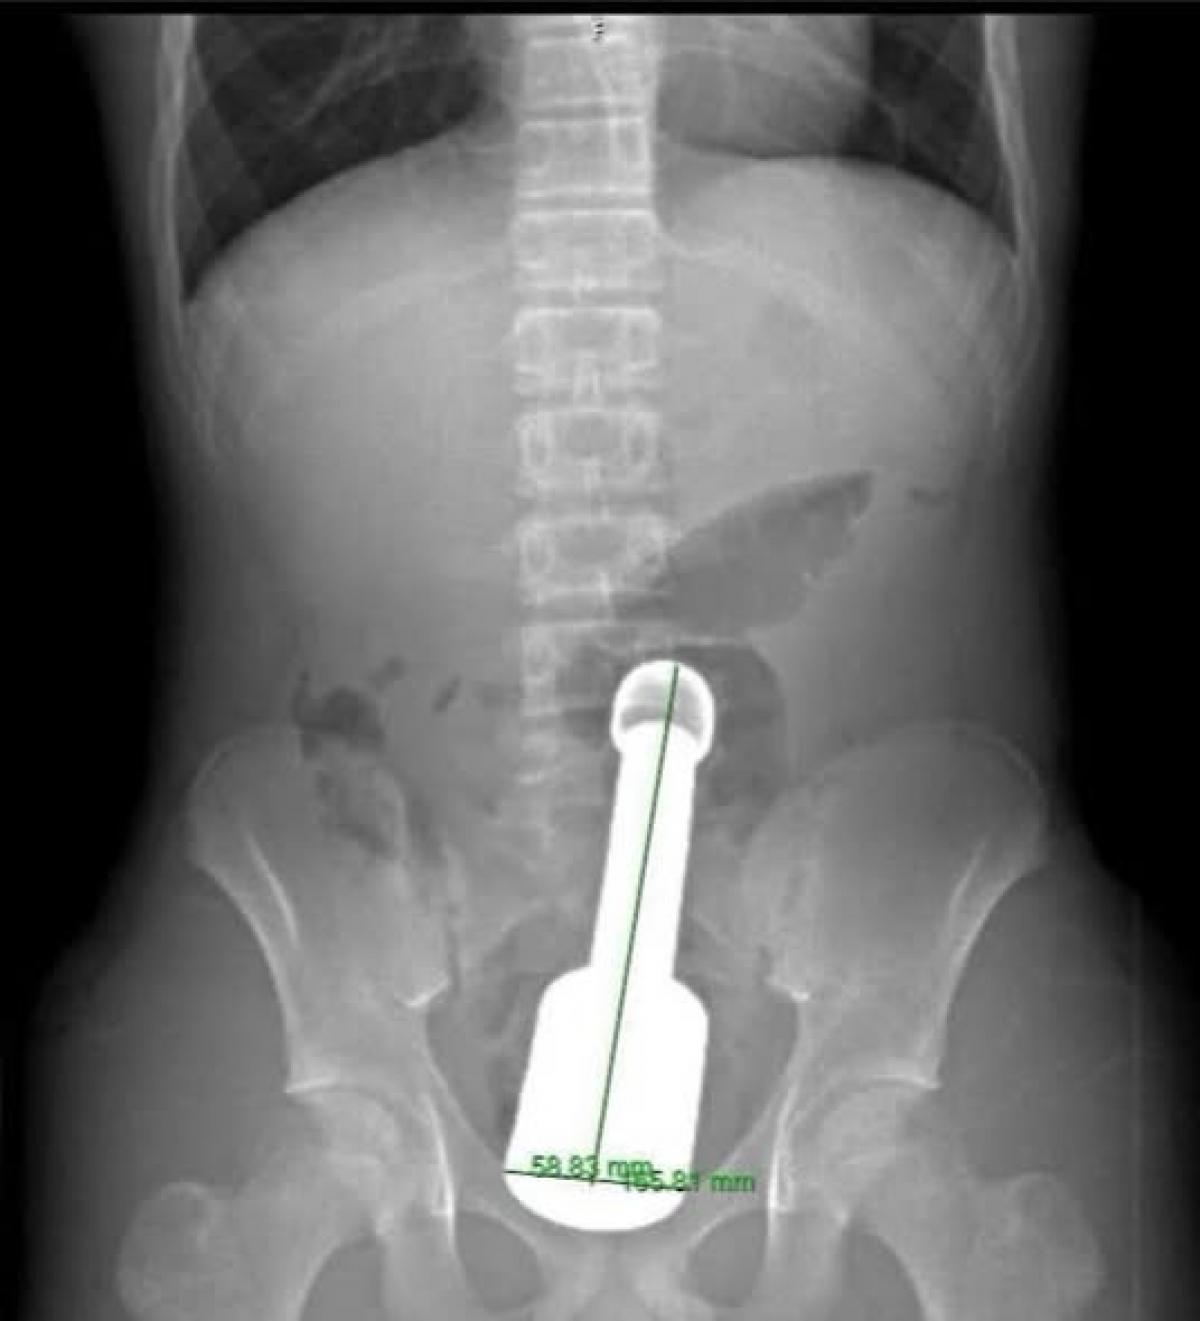

Trước đó, bệnh nhân N.K.N (15 tuổi, Hà Đông, Hà Nội) nhập viện trong đêm với biểu hiện đau tức dữ dội vùng hạ vị. Kết quả chẩn đoán hình ảnh xác định một dị vật kim loại kích thước lớn mắc kẹt sâu trong trực tràng, gây chèn ép các cơ quan vùng chậu. Đây là tình huống tiềm ẩn nhiều nguy cơ biến chứng nặng nề nếu xử trí không thận trọng.

Sau hơn 45 phút, chiếc chày dài 18cm với đường kính 6cm đã được rút ra hoàn toàn qua đường hậu môn mà không cần phải mổ phanh ổ bụng — một thành công ngoài mong đợi về mặt bảo tồn chức năng cho bệnh nhi.